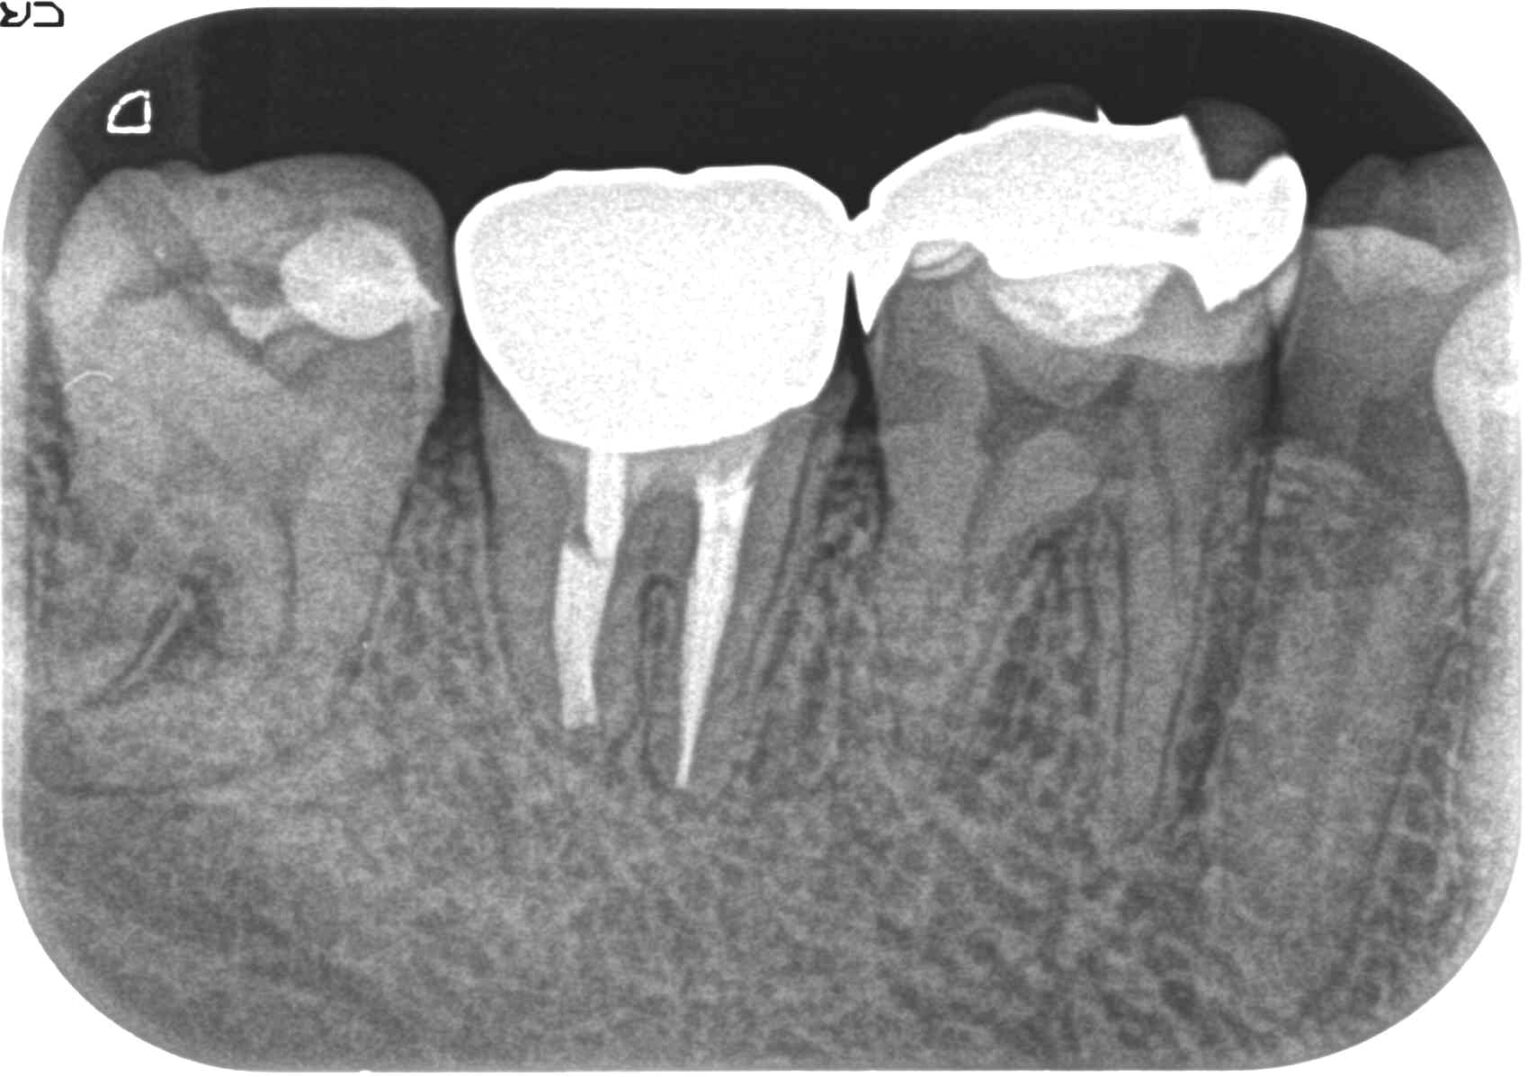

症例11外傷による打撲の為、神経が壊死し病巣が広範囲に拡がる

治療前

治療後

Before

外傷による打撲の為、神経が壊死し病巣が広範囲に拡がる

After

24ヶ月後 病巣もほぼ消失し、唇側骨板もしっかり再生されており、大変良い状態に回復している